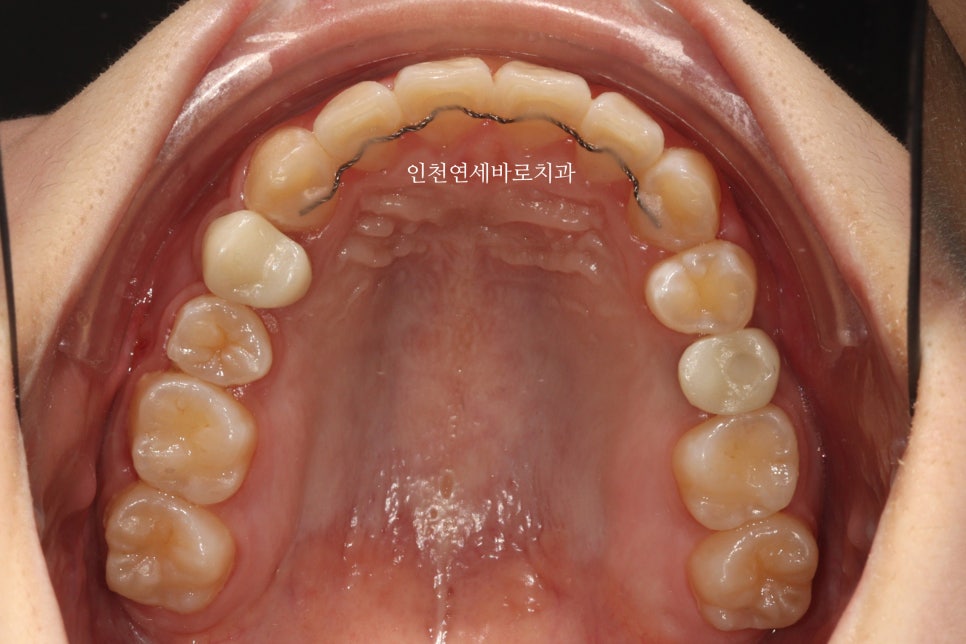

한번의 재제작을 하셨고, 치료 후 임플란트는 머리부분만 새로 제작했습니다.

처음 교정을 하러 오셨을때는 기존의 임플란트 머리 모양을 '갈아서=삭제해서' 변형시킨 뒤 교정치료를 진행했고,

교정이 모두 마무리 된 이후에 머리만 바꾸었습니다.

재제작했던 두번째 세트까지 모두 마무리 후

임플란트의 머리, 충치치료했던 치아의 크라운까지 모두 치료를 마무리 한 모습입니다.